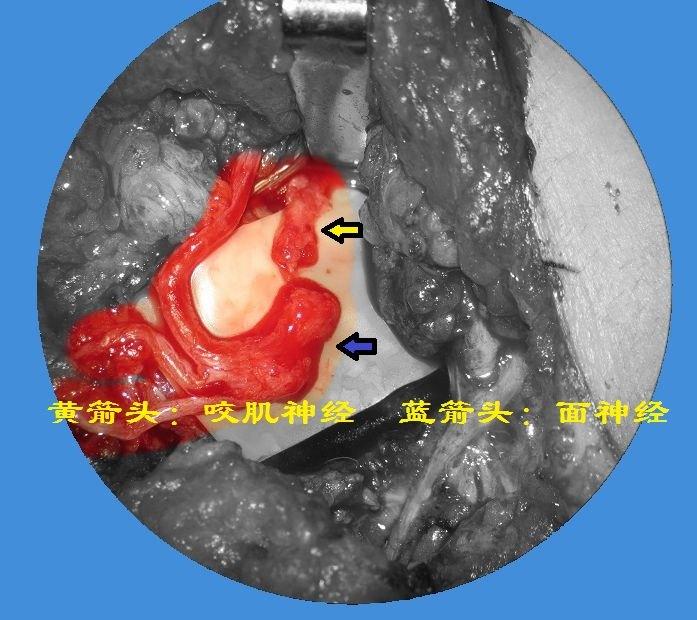

面瘫手术治疗专题一咬肌神经吻合术附病例照片